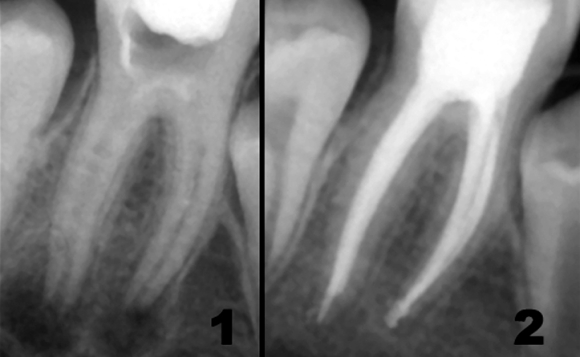

Прицельный снимок применяется для уточнения характера повреждения, оценки состояния отдельного зуба. Пример прицельного снимка до лечения и после него приведен на рисунке ниже.

Что позволяет увидеть прицельный рентгеновский снимок? На пленке подобного типа можно определить:

- качество проведенного лечения;

- наличие или отсутствие кариеса, пульпита, периодонтита;

- наличие локального пародонтита;

- травму зуба.